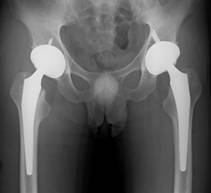

軟骨というクッションがすり減ってしまい、骨に負担がかかって痛い股関節や膝関節を新しい人工の関節に取り換える手術です。歩く時の痛みをなくすだけでなく、かなり変形してしまった関節でも,ほとんど正常に近い機能まで回復させることが可能です。手術後も激しいスポーツ以外は制限しておりませんので、ウォーキングはもちろん、自転車、ゴルフなども可能です。